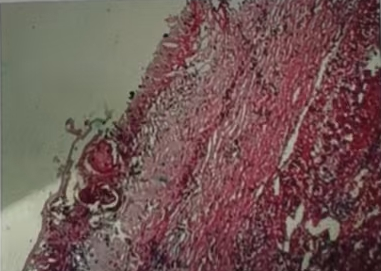

11月19日,手术团队在术中联合控制中心静脉压,采用Pringle法间断阻断肝门,精准定位外囊与肝组织的界限,成功避免了损伤门脉分支及胆管等重要结构,保持囊壁完整性。术中出血仅约100ml,成功完成了“肝左叶S3切除,右叶包虫外囊摘除术”。术后患者恢复良好,病理报告显示外囊完整囊性肿物,内有粉皮样物,符合包虫病特征。